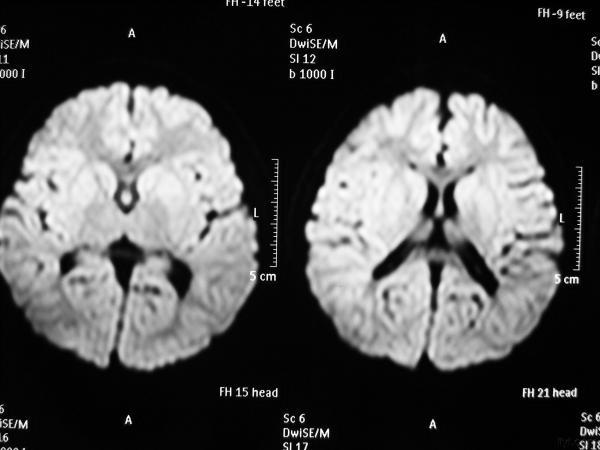

影像学发生于侧脑室周围,侧脑室扩大,脑白质减少。扩大的侧脑室外缘常不规则为其特点,多为双侧脑室同时扩大。脑白质减少,脑皮层与脑室侧缘相近。MRI T1呈低信号,T2呈高信号。